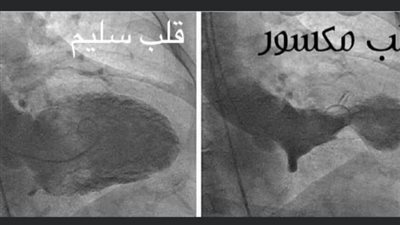

الدكتور جمال شعبان يحذر من تأثير الحزن على صحة القلب

بعد وفاة كبير مشجعي الزمالك.. الدكتور جمال شعبان: تشجيع الكرة بتعصب بيكسر القلب | بث مباشر

الجمعة 25/10/2024 07:57 م